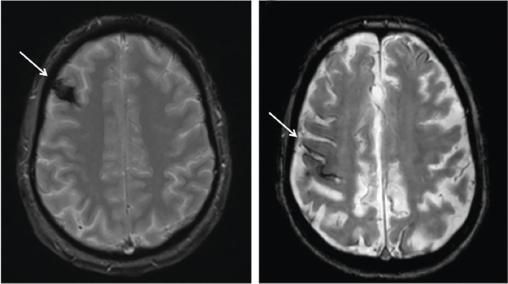

À gauche : patient de 46 ans, gaucher. Troubles du langage durant 5 minutes. Prise en charge ambulatoire pour suspicion d’AIT avec traitement par aspirine pendant 4 jours, prescrit avant l’IRM encéphalique. Découverte, sur cette coupe axiale en séquence T2*-écho de gradient, d’une malformation vasculaire frontale droite de type cavernome (flèche).